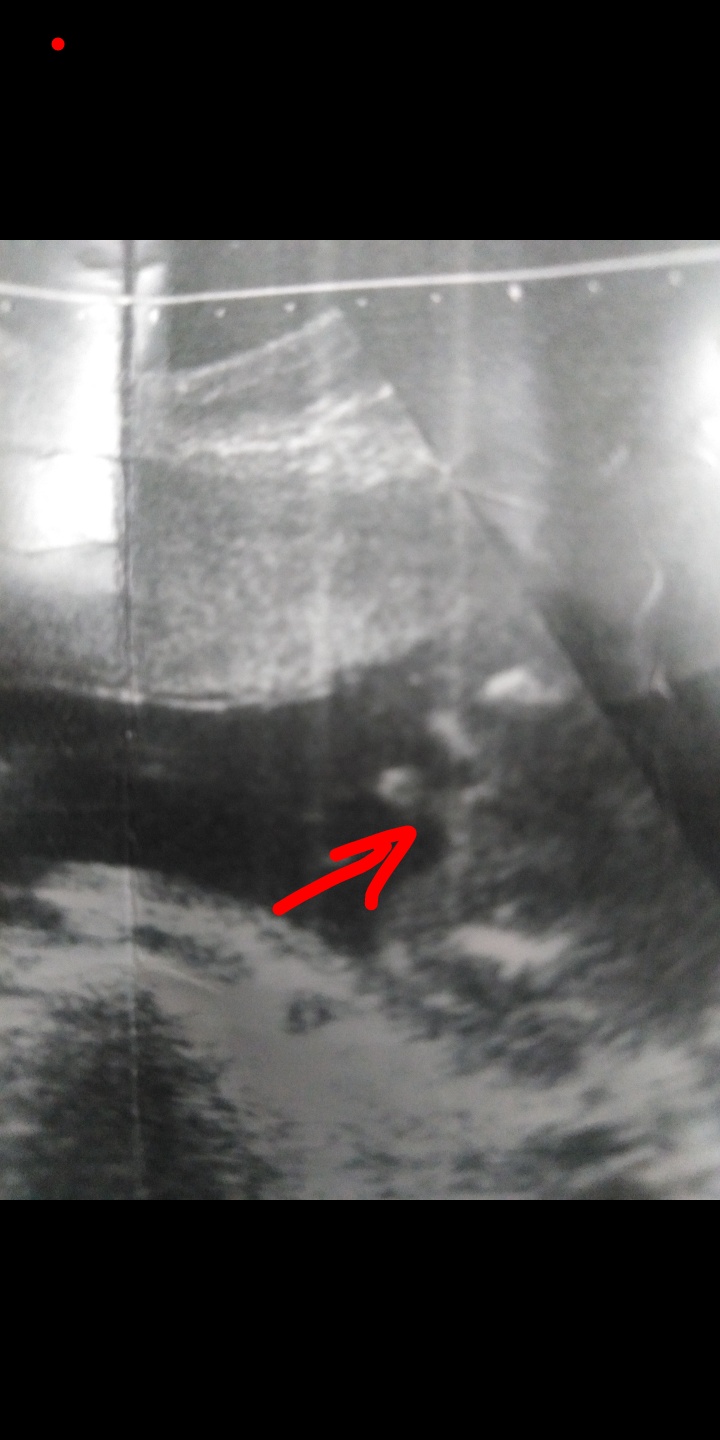

هذا هو اشرت لكم على العضو 🤦🏻♀️🙂